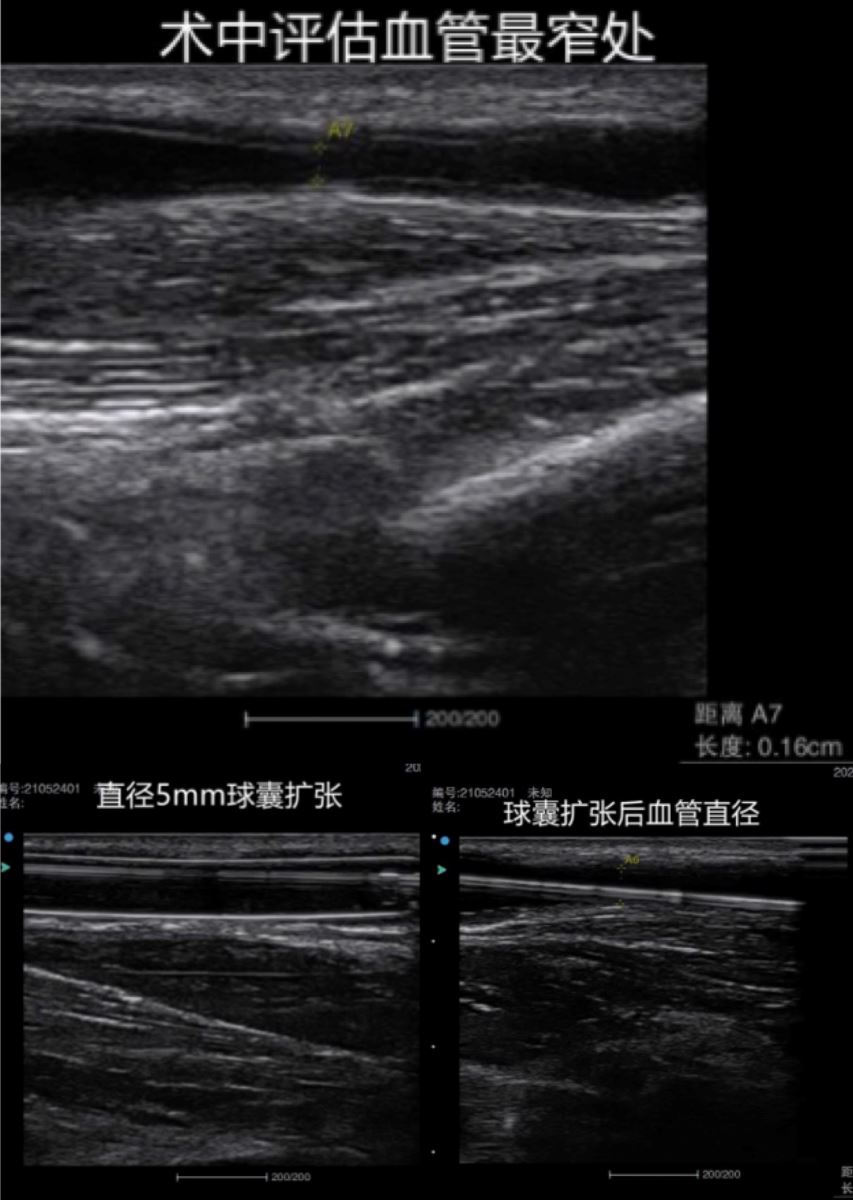

患者女性,33岁,以维持性血液透析1年,内瘘功能不良1天后入院。查体及彩超检查后发现患者内瘘回流静脉存在3处狭窄,不能维持正常血液透析治疗。时间就是生命,血液净化中心姜晖医生立即评估患者内瘘血管狭窄程度,超声提示动静脉内瘘吻合口附近流出道狭窄,狭窄率>50%,诊断自体动静脉内瘘流出道狭窄。

以往治疗此类病症均采用传统开放手术,将狭窄处截取下来,这样不仅创伤大、恢复时间慢,而且还浪费患者宝贵的血管资源。姜晖医生在向患者及家属交代病情后,决定采取创伤小、安全性高、预后效果好的超声引导下内瘘球张扩张术。

手术于5月24日下午进行,由主治医师姜晖与住院医师许若男合作完成,手术过程顺利,术后患者恢复良好,患者本人及家属对手术效果高度认可。